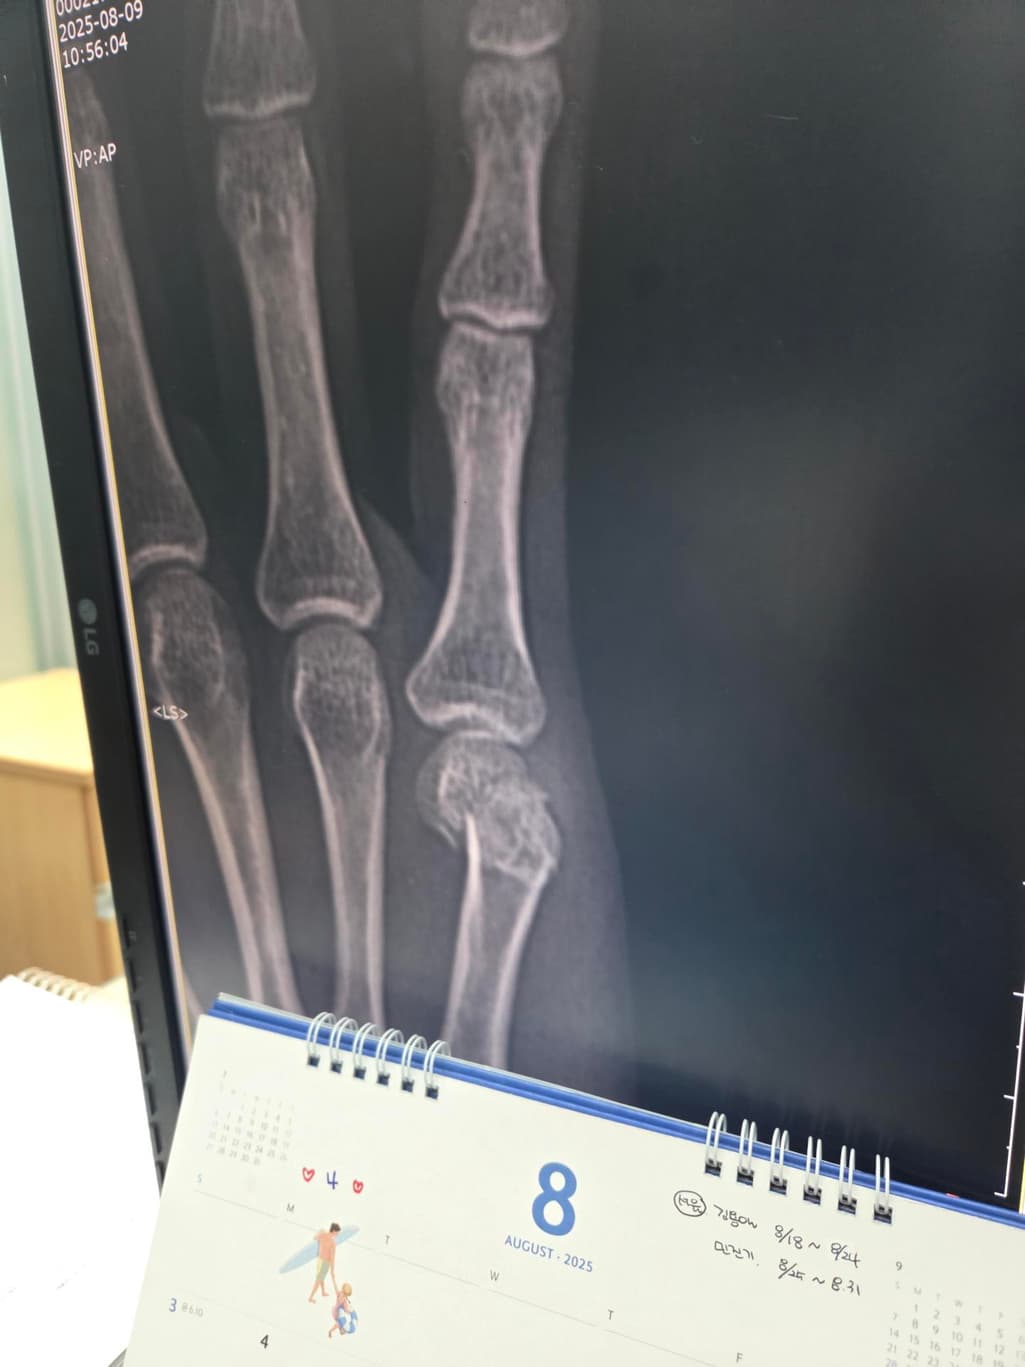

두 번째 사진을 보시면 수술한 손가락이 다른 손가락에 비해 뼈가 잘 정렬이 안 된 것 같아서요. 수술적으로 잘못된 부분이 있는지 알려주시면 감사하겠습니다.

엑스레이상으로는 금속 핀을 박은 수술로 보이며 사진상 정확한 상태 확인이 어렵긴 하지만 크게 정렬이 틀어지거나 문제는 없는 것으로 보입니다.

제가 직접적으로 수술의 판단해 드리긴 어렵습니다. 다만 사진상으로는 금속 핀 고정으로 뼈 정렬을 잡은 흔적이 보이며 수술 직후에는 약간의 틀어짐이 있어도 시간이 지나면서 유합과정에서 교정되는 경우가 많습니다.뼈가 완벽히 일직선으로 맞지 않아도 기능 회복에는 큰 지장이 없는 경우도 흔합니다!

우선 현재로썬 수술적인 부분에선 큰 문제가 없어보이지만 사진상 정확히 볼 수 없기에 현재로썬 전문의에 소견을 들어보시길 추천드립니다.